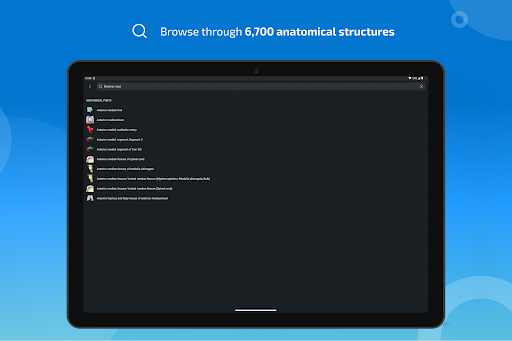

* اعثر على الأجزاء التشريحية الخاصة بك بسهولة أكبر بفضل ميزة البحث الجديدة والأكثر سهولة وقوة

* تحسين أداء البحث عن البنية التشريحية